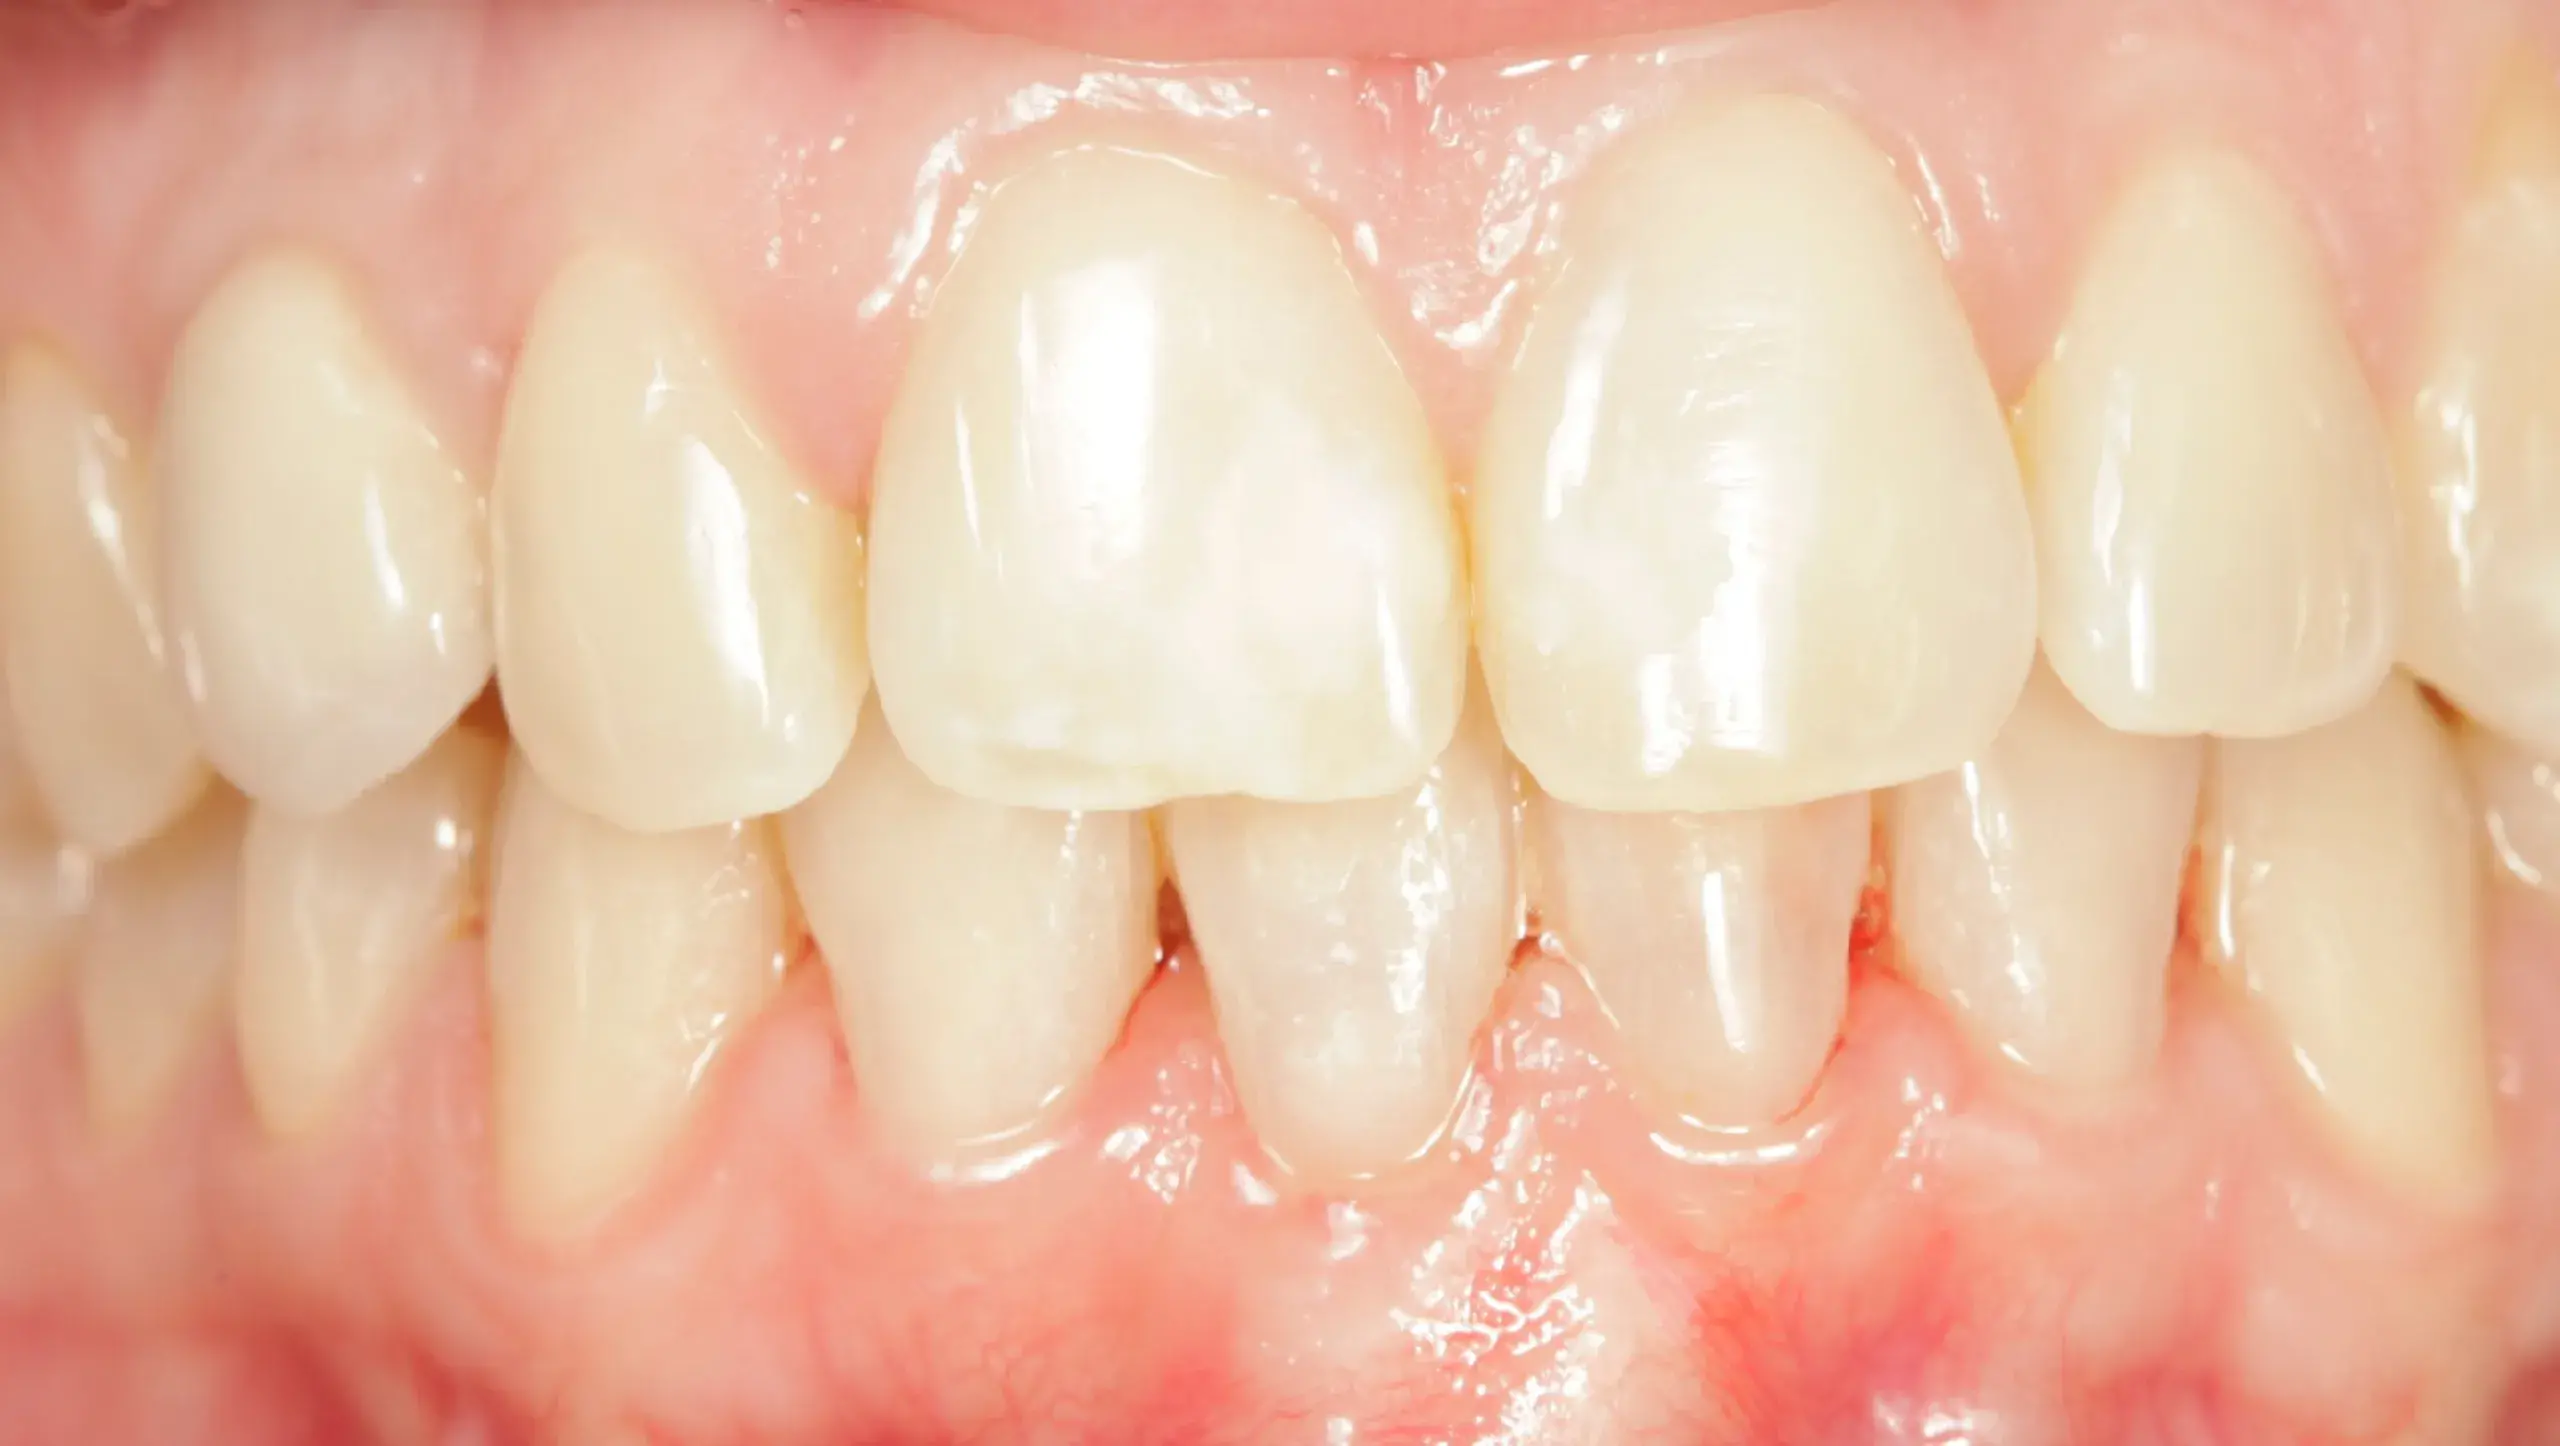

Caso clínico 7: Restauración de diente

Caso clínico 7: Restauración de diente Este caso clínico presenta un diente que inicialmente parecía estar comprometido hasta el punto de necesitar extracción , pero mediante una restauración adecuada se…